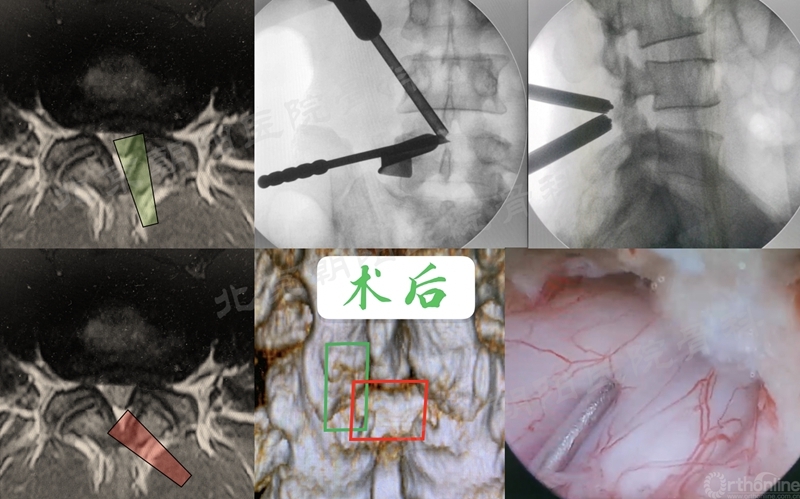

1、 镜下迷失——减压部位错误

#1例UBE,术前计划减压范围如绿色部分,术中减压操作集中在了硬膜背侧,甚至多数时候在对侧操作,实际减压部位在红色部分,使椎管减压的效果不理想。

2、 镜下迷失——节段错误

#14例UBE,术中迷路,L5/S1突出做到了L4/5右侧透视图),及时转开放减压。

本例手术镜下迷失原因总结:

① 术前设计切口靠近端,本期望利于椎板钳减压椎板,弄巧成拙;

② 定位后通道方向没有记牢,操作时角度改变了;

③ 做L5/S1体位摆放应注意把上半身摇高,使L5/S1水平;

透视正位应将L5/S1间隙标准化,否则定位不准;

⑤ 患者肥胖,脂肪软组织厚;

⑥ 镜下结构不对马上透视。